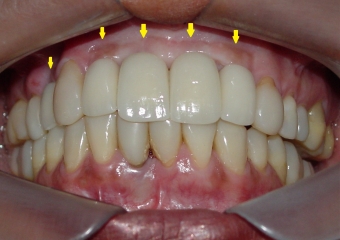

Sorriso final, do caso terminado em novembro de 2013